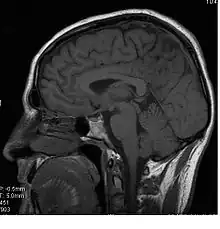

Le corps calleux (ou corpus callosum) est une commissure (moyen d'union entre deux parties) transversale du cerveau présente chez les mammifères placentaires[1]. C’est un faisceau d'axones (fibre nerveuse qui correspond au prolongement long, mince et cylindrique du corps cellulaire d'un neurone) interconnectant les deux hémisphères cérébraux. C'est la plus importante commissure du cerveau, car elle relie les huit lobes du cerveau entre eux (lobes frontaux, temporaux, pariétaux et occipitaux gauche et droit). Le corps calleux assure donc le transfert d'informations entre les deux hémisphères et ainsi leur coordination. Les autres commissures sont le fornix, le cingulum et la commissure blanche antérieure.

D’avant en arrière, on peut délimiter trois structures :

- le « genou » et le tiers antérieur du corps calleux (bec ou rostrum) sont ainsi formés par les fibres qui unissent les deux cortex (lobes) frontaux ;

- le tiers moyen (ou tronc) est formé par les fibres qui unissent les cortex pariétaux et temporaux ;

- la partie la plus postérieure, (bourrelet ou splenium), est formé par les fibres qui unissent les deux cortex occipitaux.